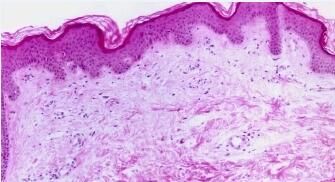

大部分患者将荨麻疹与湿疹分的不太清楚,认为两者的症状相同,归根结底是对荨麻疹与湿疹的区别较为模糊,那么下面就请北京京城皮肤医院为您详细的服务。

小儿荨麻疹多是过敏反应所引发的,其较为多见的可疑病因首先是食物,其次是病毒感染。因年龄的不同,饮食种类不同而造成荨麻疹的原因也不同,比如婴儿以母乳、奶制品喂养为主,可引发荨麻疹的原因多与奶制品的添加剂有关。这是荨麻疹与湿疹的区别。因此化脓性咽炎、上呼吸道感染等病症成为荨麻疹的诱发的重要因素。